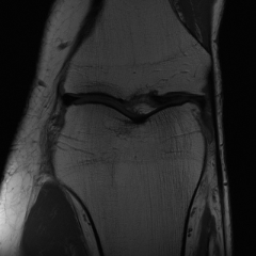

Tumour Information Preservation. For the brain tumor segmentation, we use a Swin UNETR model[28, 70], trained with random rotation, and intensity as data augmentation. On the test set with human ground-truth annotations (), the brain volumes generated from single slice input preserve the volume of the different tumour components (paired t-test, for all 3 classes). In Figure 4, we highlight the tumor profiles of the generated MRIs compared to the ground truth tumour profile. The real MRI Dice score in the test set is 85.15 while the generated MRIs from a single slice have a dice score of 83.09. This shows how the generated MRIs indeed preserve the tumor information and can act as an affordable and informative pseudo-MRI, before conducting an actual costly MRI examination in hospitals. More detailed results are provided in supplementary material.

5.3 Out-of-Domain Generalisation

One way to test the generalization capability of the trained X-Diffusion is to test it on a completely different domain from an MRI dataset not seen during training. We report the single-slice results on NYU fastMRI [37, 82], a knee MRI dataset, using the X-Diffusion trained on the BRATS brain MRIs. The results are shown in Figure 9 and Table 2. It shows how successfully X-Diffusion is able to generate knee MRIs from a single image, despite not seeing knees at all in training. To qualitatively assess how realistic our generated 3D volumes were (produced from a single slice), we gave 20 generated examples alongside their real MRI counterparts to an expert orthopaedic surgeon. He was then asked to identify the real example from a given pair. The surgeon identified with certainty only 10 real knee MRIs out of 17, while could not decide on the remaining 3 of the 20 MRI pairs. This further validates the generated out-of-domain MRIs.